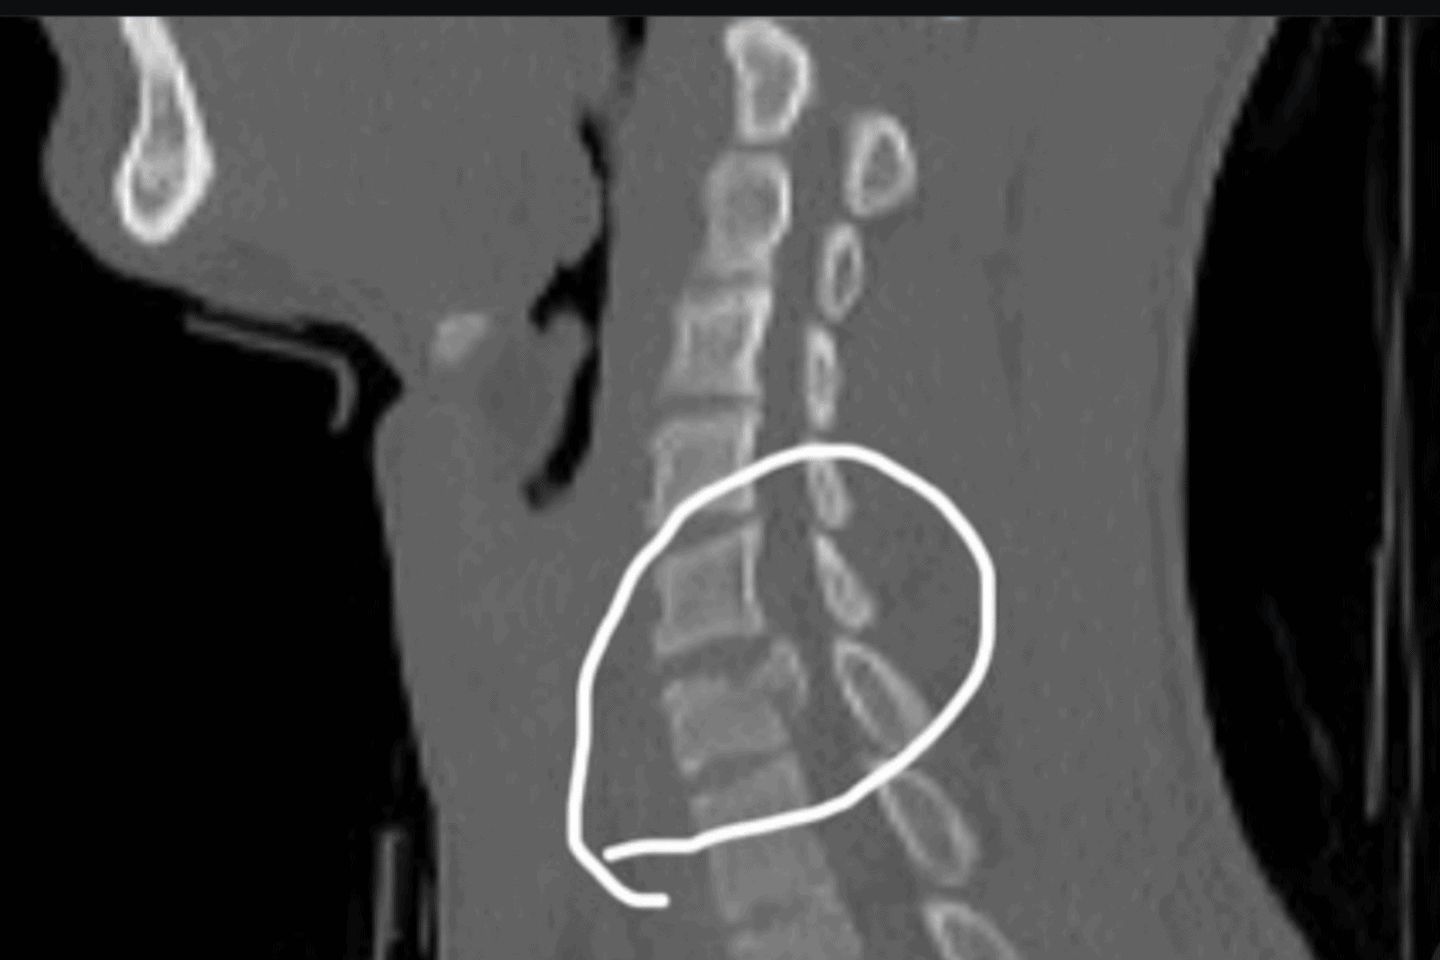

Doch nun der nächste Rückschlag: In Heat drei in Bitche wurde Krug in der Whoop-Sektion nach der ersten Startkurve unverschuldet in einen Startcrash verwickelt. Ein Konkurrent touchierte sein Hinterrad, woraufhin Krug stürzte und ein anderer Fahrer unglücklich in seinen Nacken fuhr. Die Diagnose: Bruch des Halswirbels C6.

Am Montag wurde er in Saarbrücken operiert, wo ihm ein künstlicher Wirbel sowie zwei künstliche Bandscheiben eingesetzt wurden. Es geht ihm den Umständen entsprechend gut und laut den Ärzten, soll er das Krankenhaus voraussichtlich ohne bleibende Bewegungseinschränkungen noch diese Woche verlassen können. Wann er ins Renngeschehen zurückkehren kann, ist zur Zeit allerdings unklar.